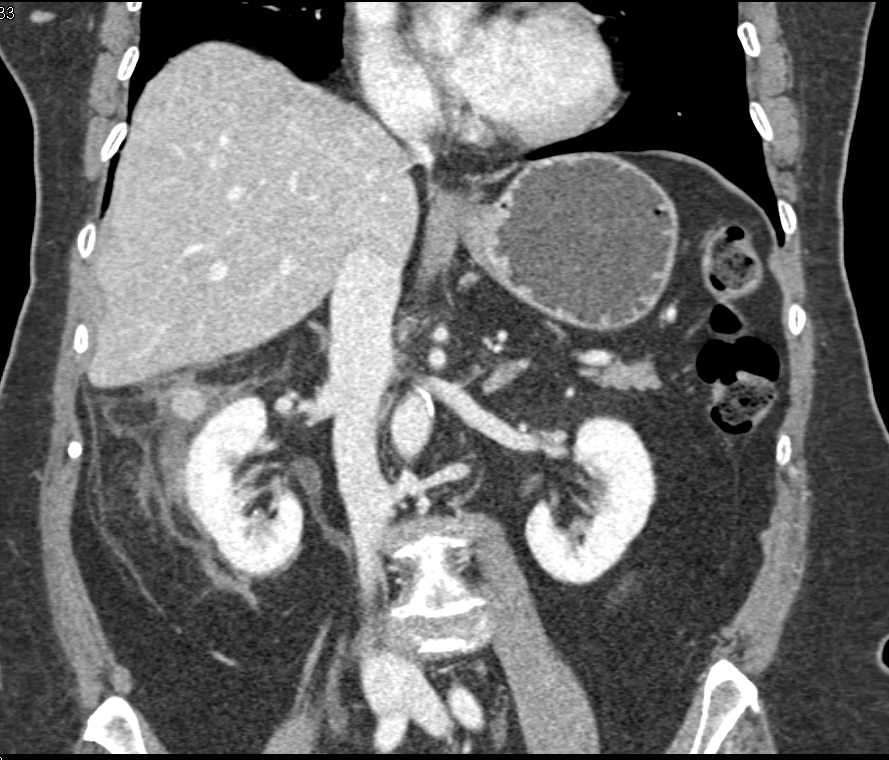

Right Perirenal Bleed